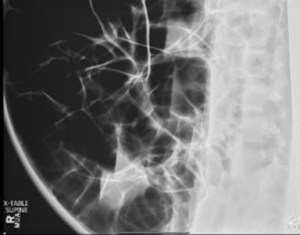

ED abdominal images and workup:

Significant lab results included a non-anion gap metabolic acidosis.

Figure 2. supine cross table abdominal plain film obtained in the ED.

Figure 3. AP abdominal plain film obtained in the ED.